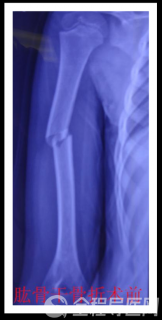

有人说,弹性髓内钉的出现是上天对儿童的恩惠。的确,弹性髓内钉是治疗小儿长管状骨骨骨折的一种理想、可靠的内固定方法。

该技术先将骨折闭合复位,通过微小的切口将特制的弹性髓内钉置入骨髓腔,达到固定骨折的目的。适用于肱骨,股骨,尺桡骨等部位的常见骨折。